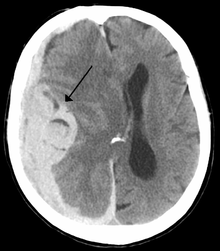

Midline shift

Midline shift is a shift of the brain past its center line.[1] The sign may be evident on neuroimaging such as CT scanning.[1] The sign is considered ominous because it is commonly associated with a distortion of the brain stem that can cause serious dysfunction evidenced by abnormal posturing and failure of the pupils to constrict in response to light.[1] Midline shift is often associated with high intracranial pressure (ICP), which can be deadly.[1] In fact, midline shift is a measure of ICP; presence of the former is an indication of the latter.[2] Presence of midline shift is an indication for neurosurgeons to take measures to monitor and control ICP.[1] Immediate surgery may be indicated when there is a midline shift of over 5 mm.[3][4] The sign can be caused by conditions including traumatic brain injury,[1]stroke, hematoma, or birth deformity that leads to a raised intracranial pressure.